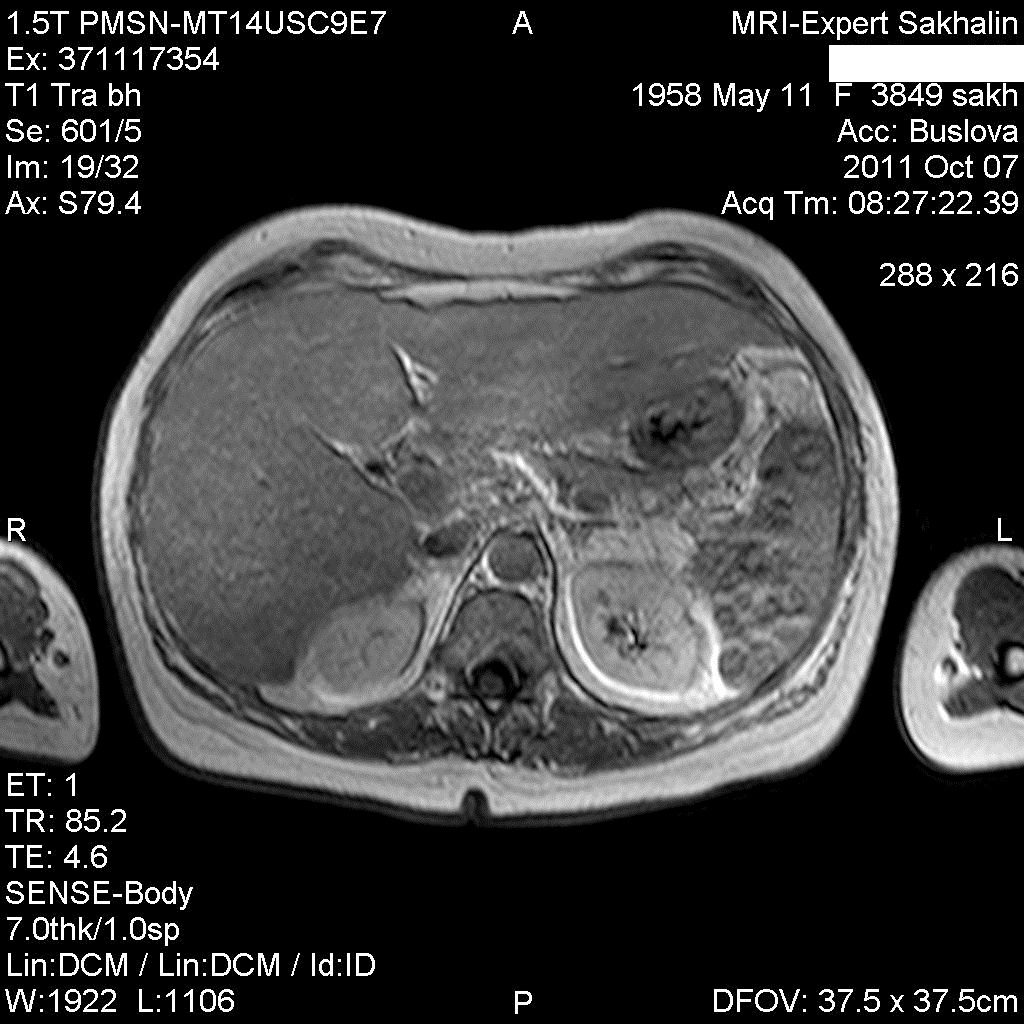

Изменения печени и селезенки.

Сегодня приходила женщина на исследование с жалобами на боли в подреберье, явления диспепсии.

похоже на метастазы, особенно в селезёнке, с центральным распадом. Хотелось бы и Т1 ВИ увидеть.Чётче на них видны были бы видны очаги в печени и вообще метастазы меланомы например могут иметь усиленный сигнал по Т1. а то в печени как будто множественные гипоинтенсивные очаги с отёком, но не совсем уверен, выглядит как просто пёстрая картинка.

а не лимфома это ? печень мне видится в  виде узлового поражения  и очаговое поражение селезенки.

Метастатическое поражение печени и селезенки, характерно для мелко-клеточного рака легкого.